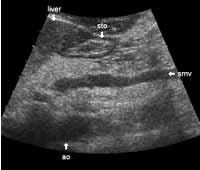

The following study describes anatomical landmarks in the ordinary pancreas of a thin patient:

Transverse planes in caudal direction: